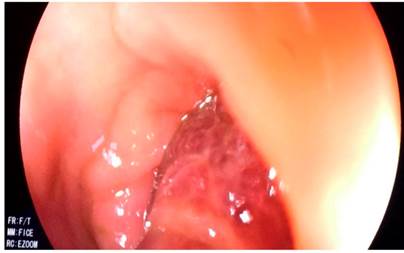

Figura 3 Paso del lazo hemostático (endoloop) previo a la polipectomía.

Se decidió entonces realizar una polipectomía endoscópica. Además, ante el tamaño del pedículo, se optó por insertar un lazo hemostático (endoloop). Luego de ello, se usó el asa de polipectomía y se resecó el pólipo (Video 1).